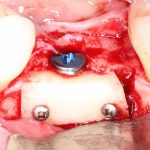

Напомню, что для этой работы я выбрал субкрестальные имплантаты Ankylos C/X. Они прекрасно сочетаются с любым методом остеопластики.

Я не планирую установку супраструктур или коронок, поэтому на уровень первичной стабильности можно положить болт. Даже наоборот — чем меньше крутящий момент при установке, тем лучше. Для имплантатов Ankylos и подобных им, это особенно важно. В общем, момент силы при установке — не более 10-15 Нсм.

Ремарка: имплантаты с предустановленными имплантодержателями хороши тем, что с ними легко контролировать позиционирование имплантатов. В случае с Ankylos С/Х - еще и крутящий момент. Имплантодержатель должен отсоединяться от имплантата с легким щелчком. Если его клинит, и тебе приходится прикладывать для этого усилия, то ты, однозначно, превысил момент силы во время установки имплантата. Следовательно, жди проблем.

Глянем на то, что получилось:

Осталось адаптировать костный блок (убрать острые края), проверить его фиксацию и, при необходимости, добавить винты. Десятисекундное дело.